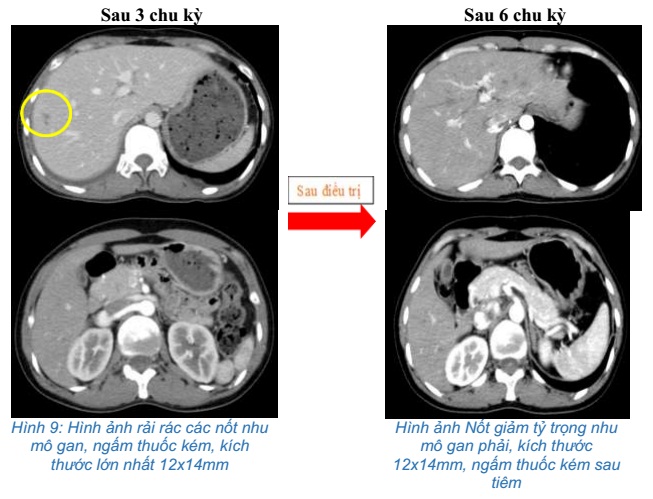

- Chụp cắt lớp vi tính bụng: Rải rác các nốt nhu mô gan, ngấm thuốc kém, kích thước lớn nhất 12x14mm

So sánh hình ảnh cắt lớp vi tính bụng trước và sau điều trị 3 chu kỳ:

- Chụp cắt lớp vi tính bụng: Nốt giảm tỷ trọng nhu mô gan phải, kích thước 12x14mm, ngấm thuốc kém sau tiêm

Sau 6 chu kỳ điều trị:

Sau điều trị hoá trị kết hợp Pembrolizumab cho thấy: U phổi giảm kích thước, hạch trung thất không còn, chất chỉ điểm khối u CEA, Cyfra 21-1 giảm về giới hạn bình thường, tổn thương di căn gan các nốt nhu mô gan giảm bớt. Bệnh nhân không gặp tác dụng phụ đáng kể nào trong quá trình điều trị.